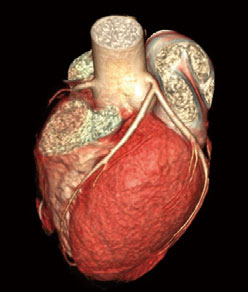

CT冠状动脉成像图

CT冠状动脉造影(CTA)是经静脉注射造影剂后利用螺旋CT扫描再经过计算机处理重建得出的心脏冠状动脉成像的一种检查方法,能够清楚的呈现冠状动脉形态,诊断有无狭窄改变。这种技术是从手臂静脉输入对比剂,就象平时输液是一样,因此几乎没有创伤性,非常安全。与DSA冠状动脉造影相比较,因为不用插管,所用时间也短。

4、术前检查。由于多层螺旋CT冠状动脉造影具有强大的后处理功能,能将冠状动脉及心脏三维重建,所以也是术前检查一项重要的项目(心脏外科术前、血管病外科术前)。